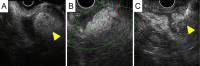

A 44-year-old woman presented to our hospital with abdominal pain. Abdominal ultrasonography and computed tomography showed a mass-like change in the lesser omentum between the liver and stomach. Esophagogastroduodenoscopy revealed a submucosal tumor-like change, and endoscopic ultrasonography (EUS) revealed that the mass was located outside of the stomach wall. We performed EUS fine-needle aspiration and diagnosed panniculitis of the lesser omentum. Based on these findings, we suggest that mass-like lesions in the lesser omentum and submucosal tumor-like changes in the anterior wall on the lesser curvature side of the stomach be evaluated for the possibility of panniculitis of the lesser omentum.